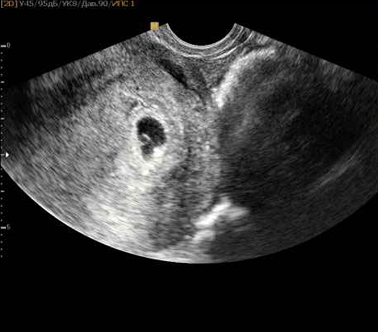

На 14-й день после переноса отмечался ХГЧ, а на УЗИ визуализировалось плодное яйцо с эмбрионом.